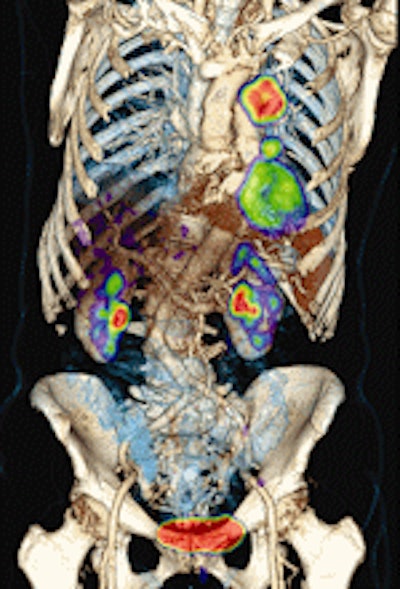

![]() |

| FDG-PET/CT with integrated contrast CT shows a large tumor in the left lung with hilar lymph node metastases. Image courtesy of Siemens Healthcare and the University of Minnesota. |